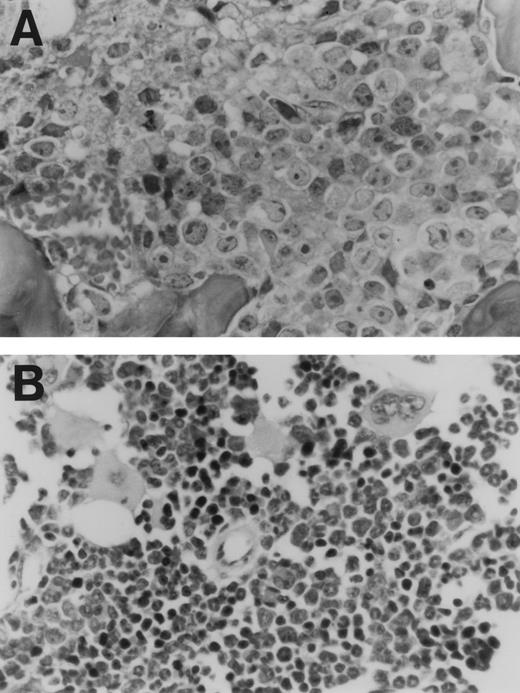

The data from two separate experiments are summarized in Fig 5. As indicated, animals that received CD44ex10 transfectants were significantly less likely to remain free of metastases than animals that were given vector-only transfectants (CD44ex10 v vector-only, 11% v 79%, metastasis-free,P < .0001). Animals that received CD44ex10 transfectants and developed hindlimb paralysis had obvious evidence of widely metastatic disease (Fig 6). For example, the bone marrow of a representative animal injected with CD44ex10 transfectants was almost completely replaced with aggressive NHL (Fig 6).

Histologic evidence of disseminated lymphoma in a nude mouse injected with a CD44ex10 Namalwa transfectant. This representative animal received a tail vein injection of CD44ex10 Namalwa cells and subsequently developed hindlimb paralysis. Thereafter, the animal was sacrificed and evaluated for additional histologic evidence of disseminated lymphoma. The bone marrow (A) is almost completely replaced with aggressive NHL. (B) The bone marrow of a control animal is included for comparison.